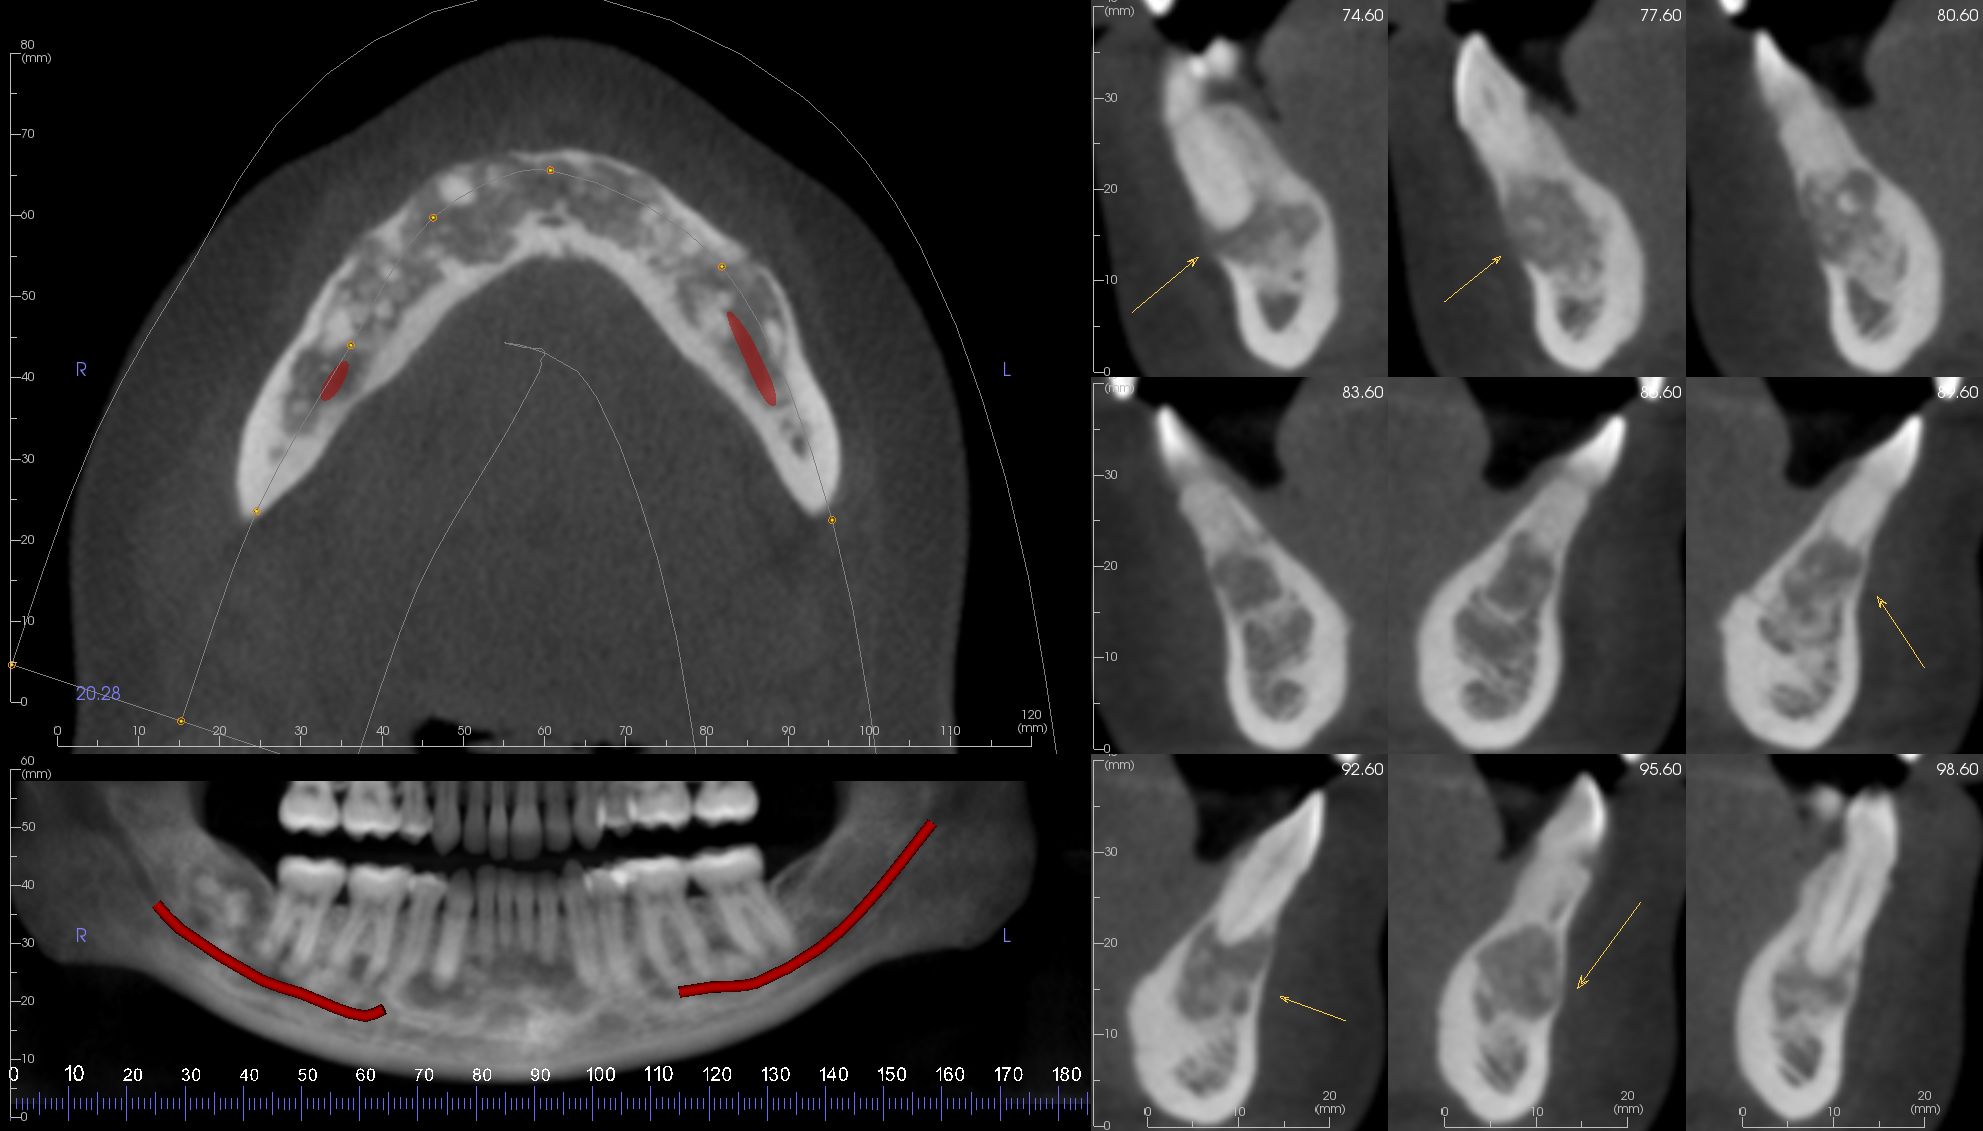

Image Portfolios visually communicate the imaging goals to you and your patient.